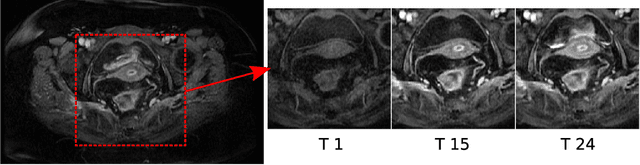

Abstract:Rectal tumour segmentation in dynamic contrast-enhanced MRI (DCE-MRI) is a challenging task, and an automated and consistent method would be highly desirable to improve the modelling and prediction of patient outcomes from tissue contrast enhancement characteristics - particularly in routine clinical practice. A framework is developed to automate DCE-MRI tumour segmentation, by introducing: perfusion-supervoxels to over-segment and classify DCE-MRI volumes using the dynamic contrast enhancement characteristics; and the pieces-of-parts graphical model, which adds global (anatomic) constraints that further refine the supervoxel components that comprise the tumour. The framework was evaluated on 23 DCE-MRI scans of patients with rectal adenocarcinomas, and achieved a voxelwise area-under the receiver operating characteristic curve (AUC) of 0.97 compared to expert delineations. Creating a binary tumour segmentation, 21 of the 23 cases were segmented correctly with a median Dice similarity coefficient (DSC) of 0.63, which is close to the inter-rater variability of this challenging task. A sec- ond study is also included to demonstrate the method's generalisability and achieved a DSC of 0.71. The framework achieves promising results for the underexplored area of rectal tumour segmentation in DCE-MRI, and the methods have potential to be applied to other DCE-MRI and supervoxel segmentation problems